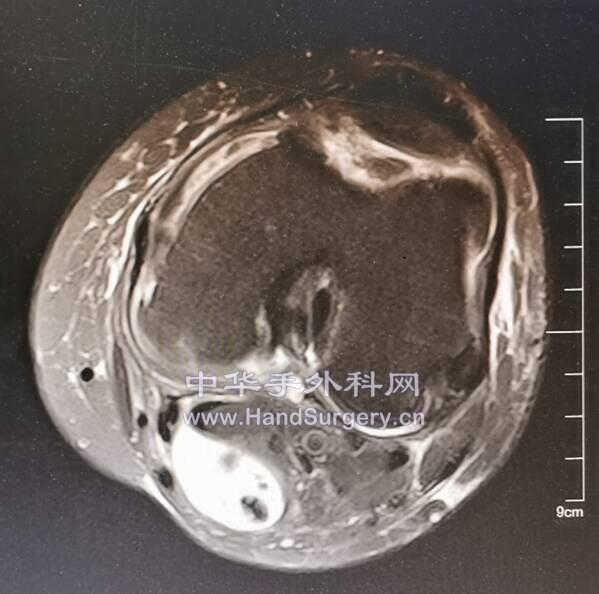

肛肠肿瘤患者,行盆腔核磁检查无意间发现股骨头肿物

囊肿影像局限,孤立,不在负重区,暂不考虑骨坏死。

会诊意见:考虑孤立性骨囊肿,不除外转移

明日一腘窝囊肿待术

12.png

13.png

患者女性,74岁

发现肿物2年,近3个月增大,走路时胀痛

肿物中间钙化,与关节囊相通

位于腘窝偏内侧,与神经血管束毗邻紧密